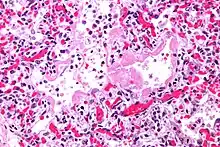

| Micrograph showing hyaline membranes, the key histologic feature of diffuse alveolar damage. H&E stain. | |

- Diffuse alveolar damage (DAD): an acute lung condition with the presence of hyaline membranes.[2] These hyaline membranes are made up of dead cells, surfactant, and proteins.[1] The hyaline membranes deposit along the walls of the alveoli, where gas exchange typically occurs, thereby making gas exchange difficult.

- The edema contributes to the deposition of a hyaline membrane (composed of dead cells, surfactant, and proteins) along the alveolar walls. Hyaline membranes are characteristic of DAD.

In order to make a diagnosis of DAD a biopsy of the lung must be obtained, processed, and examined microscopically. As described above, the hallmark of diagnosing DAD is the presence of hyaline membranes.[1] Most frequently DAD is associated with ARDS, but since there are clinical criteria (see Berlin criteria above) upon which we can diagnose ARDS, it is often unnecessary in all cases to obtain invasive biopsies of the lung. Additionally, there are limitations of the biopsy test since it is possible to sample a potentially normal area of lung even though there is DAD in the rest of the lung, resulting in a false negative.[1]